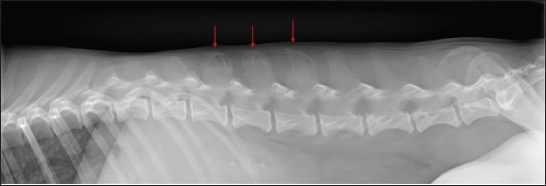

Lateral thoracic and lumbar radiographs were performed to localize any additional osteolytic foci due to the multifocal hyperesthesia. Polyostotic radiolucent moth-eaten lesions were observed at the L1, L2, and L3 dorsal processes (Fig. 3). Subsequently, an abdominal ultrasound was performed, showing heterogeneous echogenicity of the spleen and liver parenchyma and enlarged iliac lymphatic nodules. Fine needle aspirates were obtained from the vertebral lesions, spleen, and liver. The cytological evaluation of the bone lytic lesions revealed a mixed inflammatory cellular population predominantly composed of macrophages, plasma cells, lymphocytes, and non-degenerated neutrophils. Intracytoplasmic structures compatible with parasitic forms of Leishmania spp. (amastigotes) were observed inside macrophages (Fig. 4). The same structures were observed in the spleen and liver, along with extramedular hematopoiesis. Based on the previous results, a proteinogram revealed monoclonal gammopathy. An Enzyme-Linked Immunosorbent Assay anti-body anti-leishmania serology resulted in a high seropositive result, 4.93 (R.R: 0–0.9).

Fig. 3. Laterolateral radiograph of the caudal thoracic and lumbar spine. Polyostotic radiolucent moth-eaten lesions were visible in the dorsal processes of L1, L2, and L3 (red arrows).